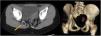

Presentamos el caso de una niña de 8 años con absceso glúteo derecho recurrente con celulitis local y drenaje purulento resistente a tratamiento local y antibioterapia intravenosa (fig. 1). No presentaba alteraciones neurológicas. El estudio de enfermedades intestinales inflamatorias fue negativo. Como antecedente personal destaca la presencia de un orificio en la misma localización desde época neonatal. Radiológicamente se muestra un trayecto fistuloso glúteo que termina en fondo de saco por encima de la fosa isquiorrectal, sin comunicación con el recto ni intraespinal (fig. 2), una malformación sacrocoxígea compleja con adelgazamiento del elevador del ano derecho y del músculo isquiocoxígeo, y una estructura osificada anómala localizada entre los músculos glúteos y la fascia endopélvica (fig. 3), con ausencia de alteraciones del sistema nervioso central y cono medular. Se realizó exéresis completa del trayecto fistuloso cuya histología correspondió a seno dérmico. Tras 2 años de seguimiento, la paciente se encuentra asintomática.